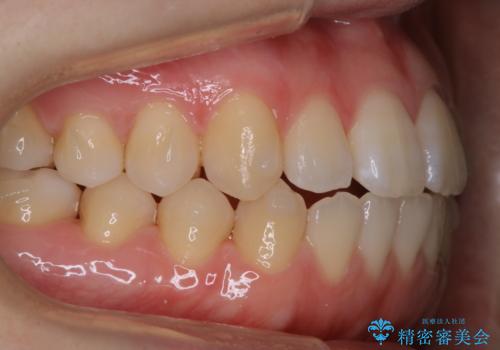

着色・ステイン除去をPMTCで

担当医 歯科衛生士